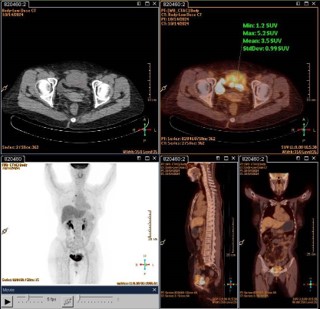

A 64-year-old woman presented with recurrent lower abdominal distension and discomfort for one week. After undergoing a pelvic CT scan, the results showed a lesion in the pelvis, a mass in front of the bladder, and it was considered to be a tumor with a high probability of malignancy (Figure 1A). The boundary between the lesion and the abdominal muscle on the front side was unclear, and there was a possibility of a vascular tumor thrombus on the left side (Figure 1B). There was a possibility of metastasis to multiple lymph nodes on the left side of the iliac external, obturator, and lateral branches of the aorta. In September 2024, due to the unclear nature of the lesion, we first performed a transurethral resection of the bladder lesion under general anesthesia to establish a definitive diagnosis and alleviate the patient’s sensation of abdominal distension. The postoperative pathological results indicated that it was a malignant spindle cell tumor of the bladder. The results of postoperative immunohistochemistry showed: UP3 (-), Myogenin (-), MyoD1 (-), CK (-), VIM (+), SMA (partially +), KI-67 (approximately 60% +), GATA3 (-), DESMIN (-). Two weeks later, the patient experienced urethral bleeding after urination without any obvious predisposing cause, accompanied by mild low back pain. After a comprehensive PET-CT examination, the results indicated a space-occupying lesion on the anterior wall of the bladder with increased metabolism, suggesting a tumor. It has not involved the gastrointestinal tract and there is no evidence of distant metastasis (Figure 2). In October 2024, a robotic-assisted laparoscopic radical cystectomy + ileal conduit operation was performed under general anesthesia. Intraoperatively, we identified this neoplasm originating from the anterior wall of the bladder, which was adherent to the abdominal wall muscles (Figure 3A). The neoplasm was large in size, grotesquely shaped, and soft in texture, resembling a cord-like structure of the intestine. It had invaded the extra-bladder fat, and tumor thrombi were found within the lumens surrounding the bladder. Upon postoperative examination of the specimen, the bladder measured approximately 8.0 x 9.0 x 2.5 cm in size. A cord-like mass measuring about 7.0 x 5.0 x 3.0 cm was visible on the anterior wall of the bladder, with a gray-brown cut surface that was soft in texture (Figure 3B). Upon repeat pathological analysis, the results unequivocally indicated that this is a malignant spindle cell tumor (Figure 3C). Immunohistochemistry indicated: CKH (-), CKL (-), EMA (-), CAM5.2 (-), VIM (+), SMA (+), CK5/6 (-), P40 (-), GATA-3 (-), Desmin (-), ALK (-), UP-3 (-), KI-67 20% (+), S-100 (-), CD34 (+), CD68 (+), ER (-), PR (-), SS18 (-), Calponin (-), MC (-), CR (-), WT-1 (-), CD10 (-), MDM-2 (-), CDK4 (-), CD117 (+), DOG-1 weakly (+), Caldesmon weakly (+), STAT6 (-) (Figure 2B). Combined with the results of immunohistochemistry, the specimen was consistent with extra-gastrointestinal stromal tumor (the maximum diameter of the tumor is approximately 7 cm, the mitotic figure is about 3 per 50 high-power fields, high risk grade).

Figure 1: (A) Pelvic CT scan reveals a mass on the anterior wall of the bladder, with CT images taken in the arterial phase, venous phase, and excretory phase from top to bottom. The mass is highly suspected to be a malignant tumor, with indistinct boundaries with the anterior abdominal muscles; (B) There is a possibility of multiple lymph node metastases in the left external iliac, obturator, and lateral branches of the aorta.